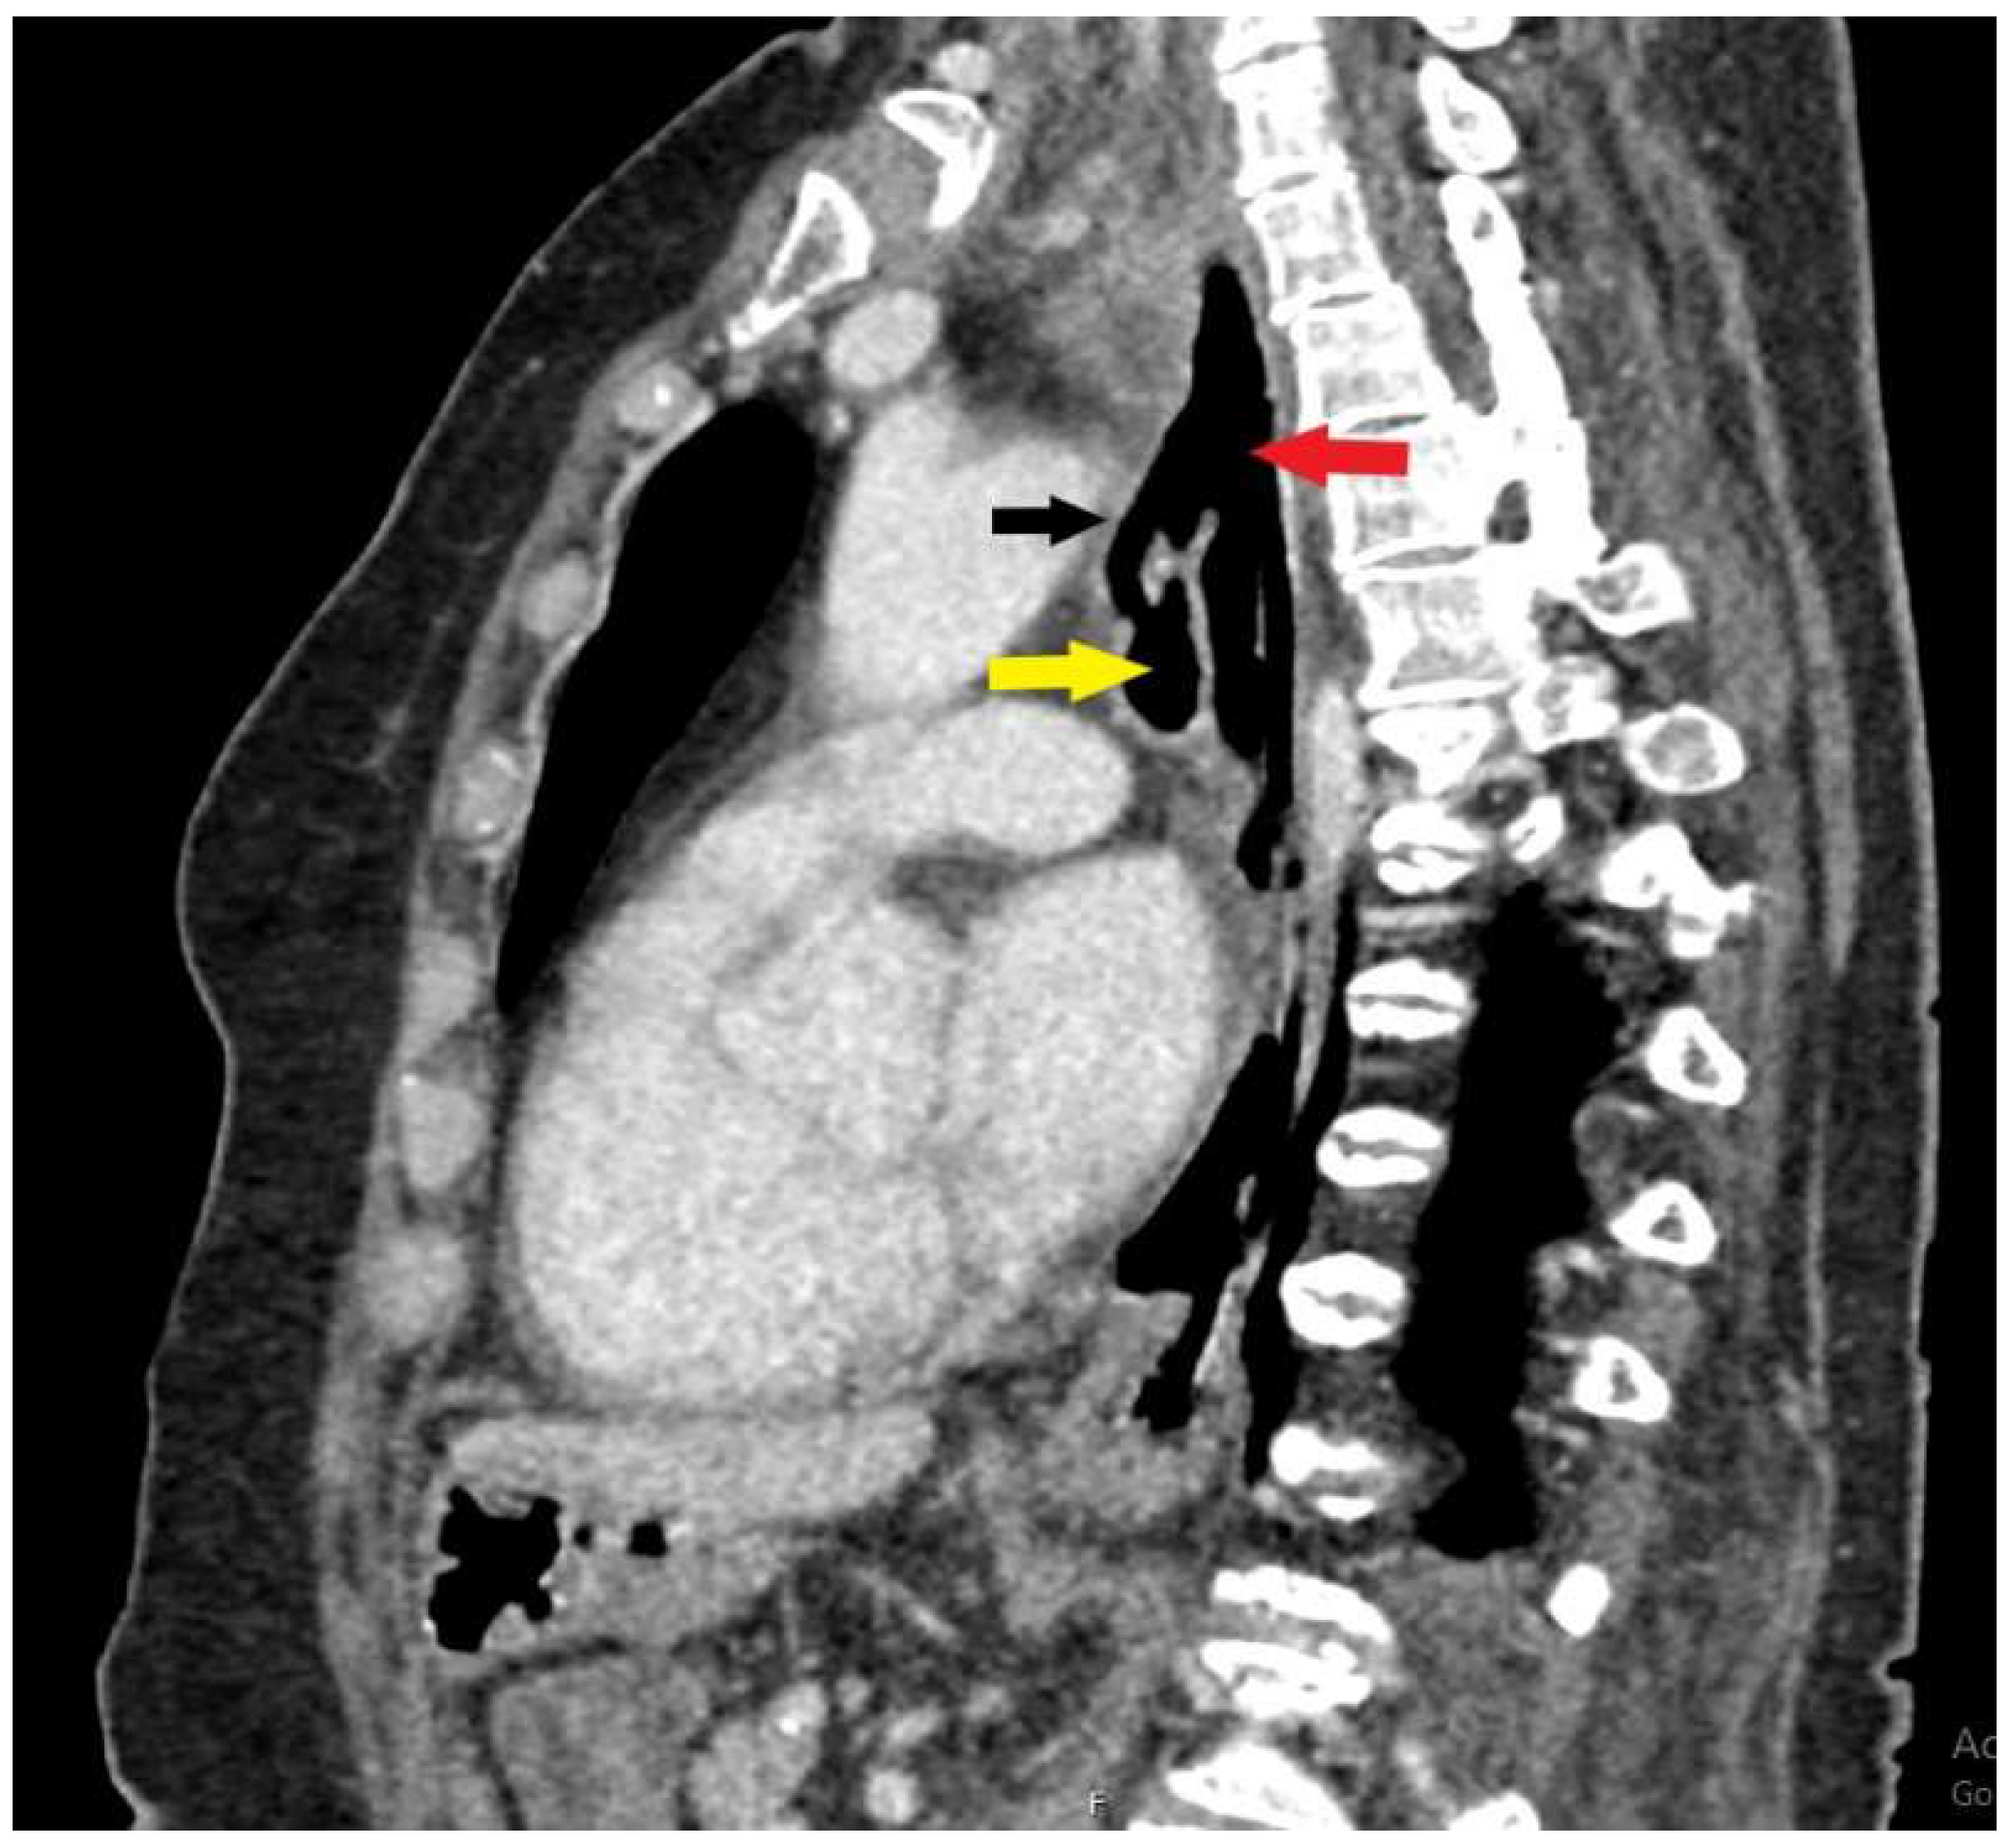

Figure 2. A sagittal CT scan shows interluminal communication (black arrow) between the lumen of the esophagus (red arrow) and the trachea (yellow arrow). There were also signs of aspiration pneumonia bilaterally and segmental pulmonary artery embolism (Figure 3).